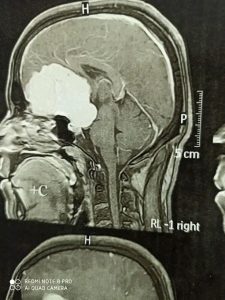

نجح فريق طبي بقسم جراحة المخ والأعصاب، بالتعاون مع قسم التخدير بمستشفي سوهاج الجامعي في استئصال اكبر الأورام من حيث الحجم بقاع الجمجمة، يبلغ ١٣٢ سنتمتر مربع، لشاب يبلغ من العمر ٢٢ سنة وانقاذه من فقد كلي للبصر، صرح بذلك الدكتور حسان النعماني رئيس الجامعة.

وأوضح الدكتور مؤمن المأمون رئيس قسم جراحة المخ والأعصاب أن الورم الذي كان يعاني منه المريض يعد من أكبر الأورام حجماً في قاع الجمجمة، واستغرقت الجراحة اكثر من ٨ ساعات، تمت خلالها استئصال كلى للورم، وتتم المتابعة الدورية له بالعيادة الخارجية بقسم جراحة المخ والاعصاب.